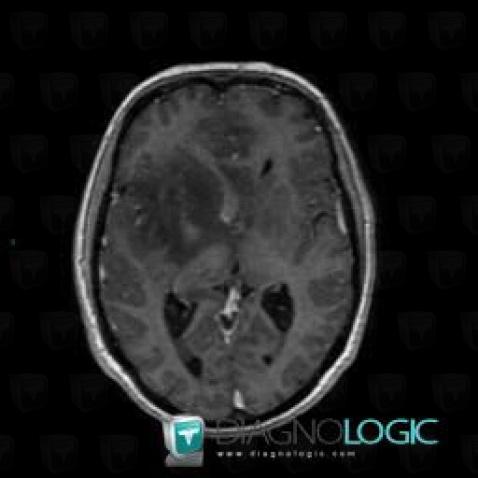

Oligodendrogliome, Noyaux gris centraux et capsule, IRM

Voici les informations spécifiques à l'image clé ci dessus:

- Diagnostic Oligodendrogliome, Localisation(s) Noyaux gris centraux et capsule, comportant les gammes Lésion en hypersignal T2 ou FLAIR des noyaux gris centraux